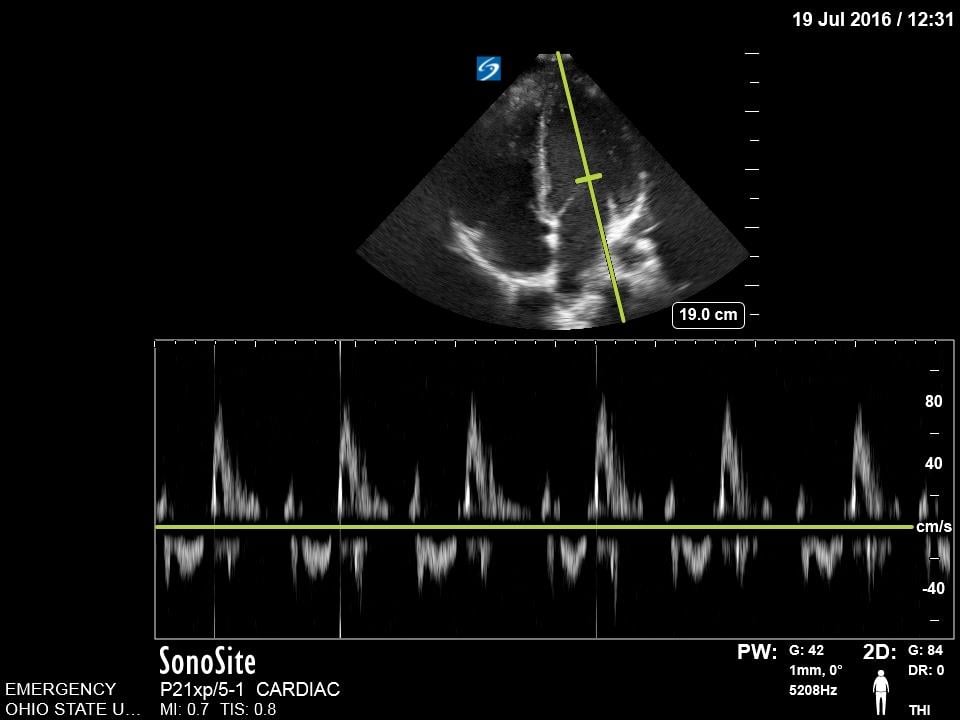

E-point Septal Separation

This is a technique that is commonly employed to provide an objective measurement of systolic function of the left ventricle. Using M-mode, capture the distance between the anterior leaflet of the mitral valve and the interventricular septum. A measure >7mm correlates with reduced cardiac function.13 This measurement may not be accurate in cases of aortic regurgitation, mitral stenosis, hypertrophic cardiomyopathy, and non-sinus rhythm.

Figure 11. Normal E-point septal separation